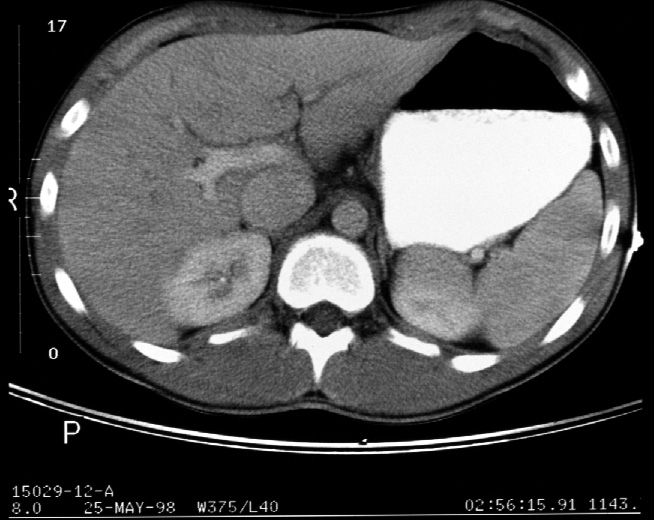

Identify -- stomach, liver, right kidney, left kidney, aorta, inferior

vena cava, diaphragmatic crura, portal vein, spleen